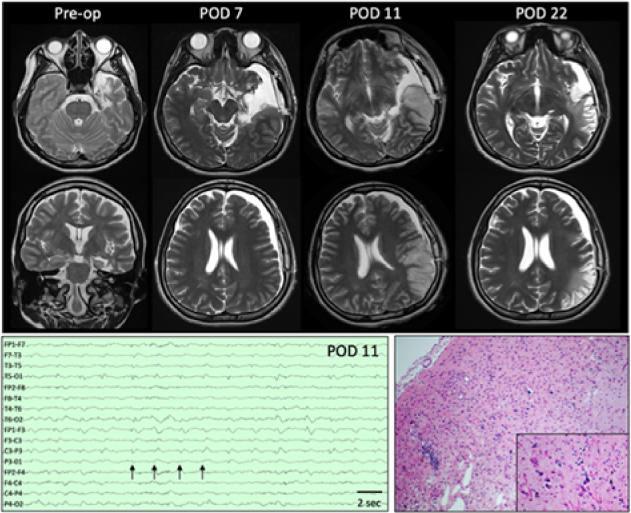

A 21-year-old right-handed female with epilepsy was admitted for presurgical work-up. Her history was significant for encephalitis 5 years earlier in China. She had focal aware seizures with auditory hallucinations and speech comprehension difficulties that occasionally evolved to bilateral tonic–clonic convulsions. Seven habitual seizures were recorded arising from the left anterior temporal lobe. Her interictal electroencephalography (EEG) showed intermittent left hemisphere slowing maximal in the anterior to mid-temporal region and occasional left anterior temporal sharp waves. Magnetic resonance imaging (MRI) demonstrated encephalomalacia in the left temporal pole, parahippocampal gyrus, and insula as well as left hippocampal atrophy (Figure 1). Interictal single photon emission computerized tomography showed left temporal hypoperfusion. Neuropsychological testing demonstrated left hemispheric language dominance and verbal memory deficits.

Figure 1: Top:Presurgical axial and coronal T2-weighted images demonstrate encephalomalacia in the left temporal pole, parahippocampal gyrus, and insula as well as volume loss in the left hippocampus. On POD 7, MRI showed a left subdural hygroma with mild mass effect and 5-mm midline shift as well as subtle signal change along the resection margin. Four days later (POD 11), MRI demonstrates left posterior temporal and parietal T2 hyperintensity that is predominantly cortical and accompanied by sulcal effacement. Additional sequences not shown demonstrate associated reduced diffusion and subtle leptomeningeal enhancement. By POD 11, overall decreased mass effect and swelling with developing extensive encephalomalacia are seen in the previously affected areas. Bottom left: EEG performed on POD 11 demonstrates lateralized periodic discharges maximum over the left hemisphere (arrows) as well as generalized slowing of background. Bottom right: Representative section of resected cortex showing features consistent with chronic sequelae of HSV encephalitis. Low-power view showing area of encephalomalcia with marked reactive astrogliosis, patchy cavitary tissue loss, mineralized neurons, and patchy mononuclear inflammation. Inset: High-power view highlighting the scattered mineralized neurons indicative of remote neuronal injury. Rare microglial nodules also identified (not shown). No evidence of active neuronophagia or other recent neuronal/tissue injury, viral inclusions or granulomatous inflammation to suggest active infection within the sampled tissue. (hematoxylin and eosin stain).

A dexamethasone taper (initial dose 4 mg Q6h) was started as a standard measure to reduce retraction swelling. On postoperative day (POD) 3, she had a habitual focal seizure with impaired verbal comprehension, head turn, and right-hand automatisms. Following this, her verbal comprehension and speech deteriorated. She was afebrile, and her white blood cell count was normal. Her anticonvulsants were adjusted. By POD 6, she suffered eight more seizures. EEG showed generalized slowing, and an MRI demonstrated subtle T2 hyperintensity adjacent to the resection (Figure 1). Maximum temperature that day was 37.6°C and white blood cell count increased to 16.1 × 109/L (4.0–11.0 × 109/L) only to fall back down to 10.2 × 109/L by POD 9. Anticonvulsants were adjusted. Her seizures were believed to have arisen from local postoperative irritation, and her dysphasia was thought to be postictal. On POD 9, she developed global dysphasia despite no obvious seizures. Continuous EEG was initiated. Three clinical and six electrographic seizures were recorded. Anticonvulsants were increased. She subsequently developed a fever of 38.4°C that increased to 40.2°C on POD 10. On POD 11, EEG showed left lateralized periodic discharges (Figure 1). A repeat MRI showed evolving T2 hyperintensity and restricted diffusion in the left posterior temporal and parietal lobes with regional leptomeningeal enhancement concerning for infectious encephalitis (Figure 1). The results of a lumbar puncture demonstrated 2.42 g/L protein (0.15–0.45 g/L), 2.6 mmol/L glucose (2.2–3.9 mmol/L), 17 × 106/L white blood cells with 67% monocytes (0–5 × 106/L), 59 × 109/L red blood cells, and xanthochromia. Empiric meningitic-dosed ceftazidime, vancomycin, ampicillin, metronidazole, and acyclovir were started. Cerebrospinal fluid (CSF) qPCR was strongly positive for HSV-1 at a cycle threshold of 24.Reference Wong, Pabbaraju, Wong and Tellier3 An autoimmune encephalitis panel including anti-N-methyl-D-aspartate was subsequently negative. Two days later, seizures had ceased and her fever abated, but she remained globally dysphasic.